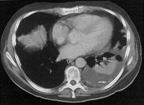

A single CT shows a malignant, left-sided pleural effusion in this patient with adenocarcinoma of the lungs. Note the intrapleural tumor nodule (arrow). Further nodularity is identified posteromedially. The atelectatic left lower lobe floats on the pleural fluid.